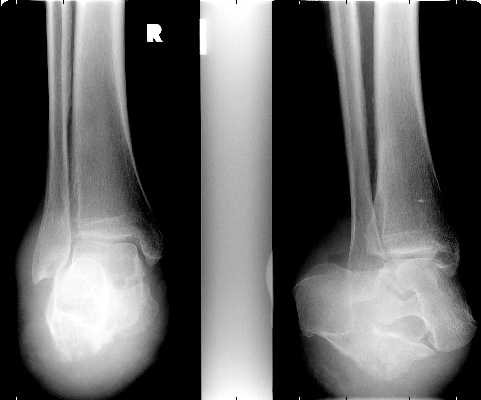

These images show an amputation through the calcaneal-cuboid and talo-navicular joints

(Chopart level).

Selected images of different patients showing the Chopart amputation.